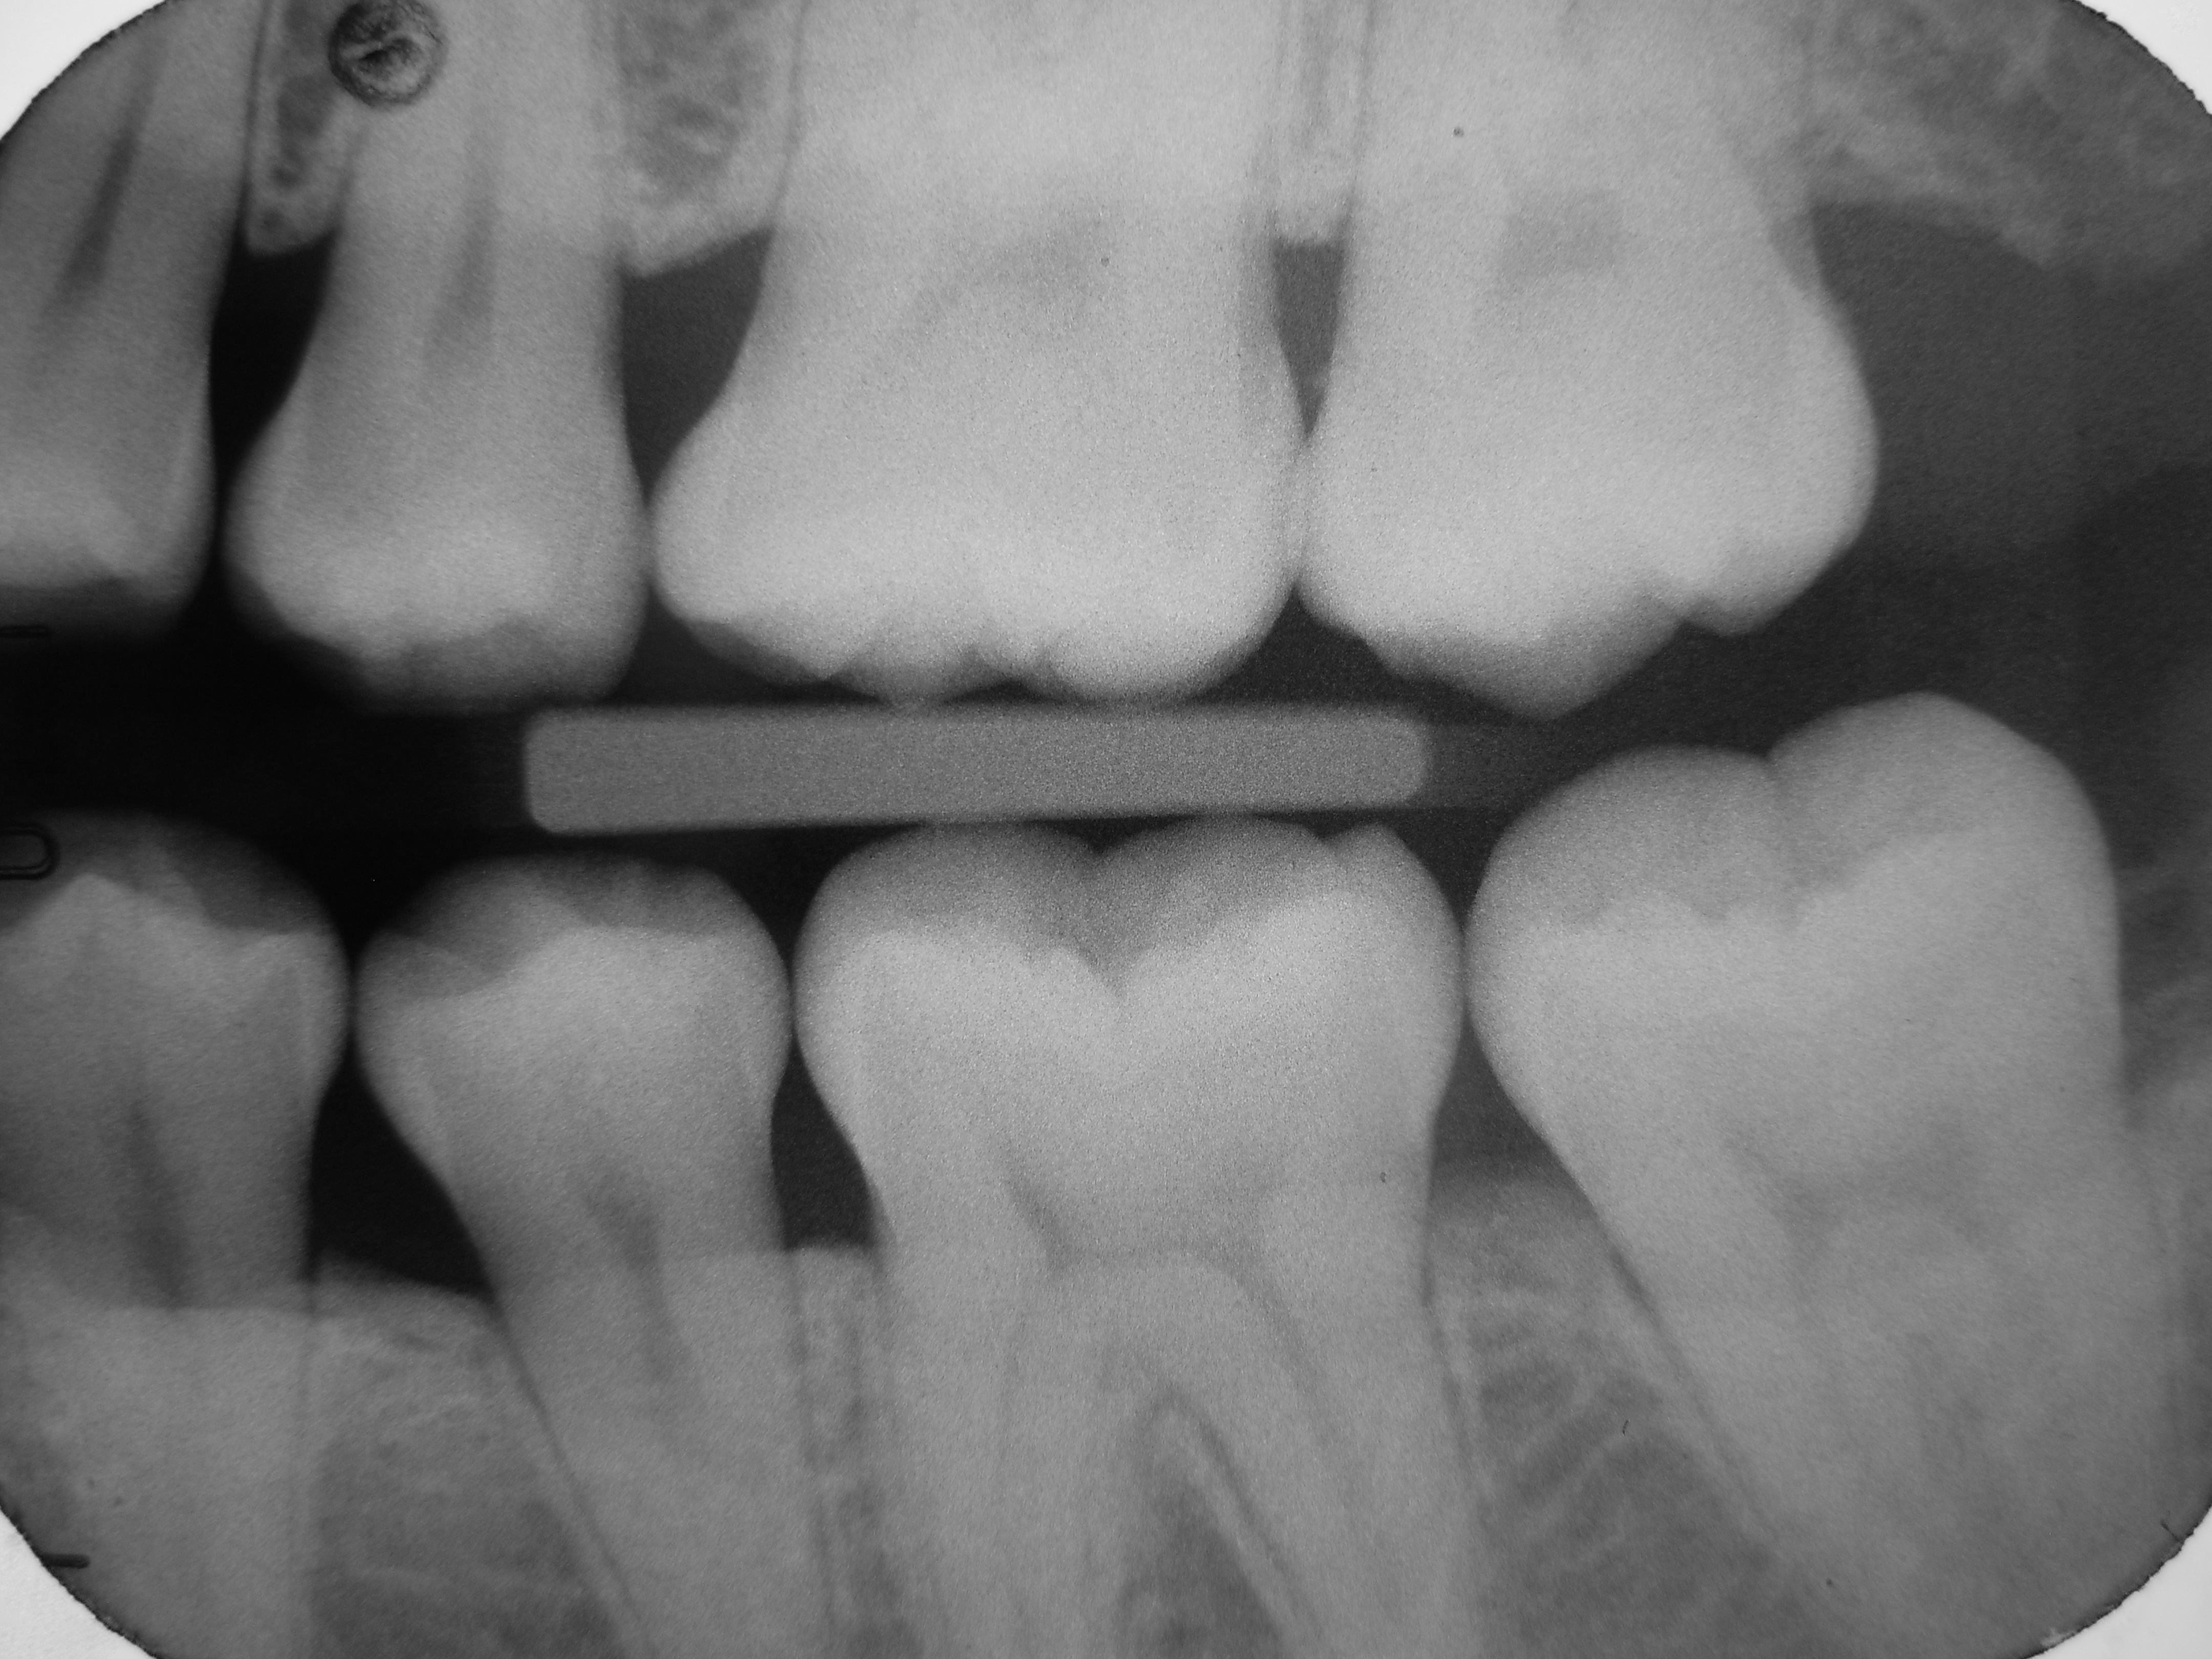

Periapical X-rays show the entire tooth, from the crown to the root, and can diagnose issues such as abscesses, cysts, or impacted teeth (see Figure 15). Bitewing X-rays are used to detect cavities between teeth, to evaluate the health of the teeth and gingiva, and to evaluate periodontal bone loss caused by gingival disease (see Figure 16). Panoramic X-rays provide a broad view of the entire mouth, useful for assessing the position of teeth, especially wisdom teeth, and detecting tumors or other abnormalities (see Figure 17).

Figure 16. Bitewing X-Ray |

![]() |

Intraoral bitewing radiograph; this film shows left side healthy dentition, no dental caries |

Source: Source: DRosenbach. https://creativecommons.org/licenses/by-sa/3.0/deed.en |